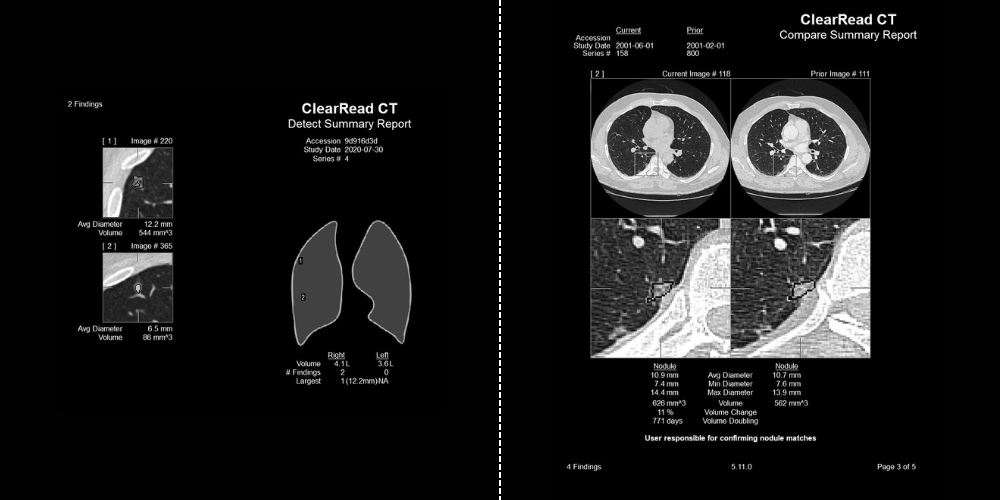

Pulmonary Nodules Automated nodule analysis, current and prior, and reporting to lighten cognitive load

- Fully-automatic nodule detection and analysis

- Quickly & easily compare nodule findings with prior exams – monitor changes in volume, diameter, and doubling time